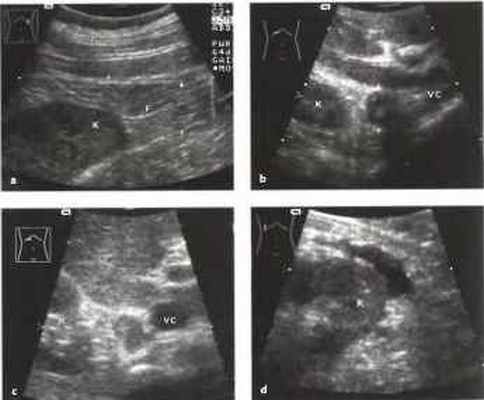

Результаты соннографии при патологии надпочечников

Надпочечники — тонкие структуры, расположенные в толще забрюшинной клетчатки, в дубликаторе почечной фасции, в поперечном срезе имеющие форму перевернутой буквы "Y” или "V”. Вопрос об эхографических размерах и структуре нормальных надпочечников является весьма сложным, поскольку в настоящее время ставится под сомнение сама возможность эхографической визуализации нормальных надпочечников во взрослой популяции, хотя литературные сведения по этому вопросу довольно противоречивы. На результатах обследований сказываются, вне всякого сомнения, такие определяющие факторы, как опыт врача и качество используемой ультразвуковой аппаратуры. При этом сразу же следует отметить, что в процессе осмотра правый надпочечник визуализируется лучше левого.

Наиболее распространенными доступами для визуализации зоны локализации надпочечников являются: справа — субкостальный (при этом, акустическим 'окном’ является правая доля печени и нижняя полая вена), слева — интеркостальный по левой аксиллярной линии. Газовый пузырь желудка мешает визуализации левого надпочечника, с этой стороны нет хорошего "акустического окна”, в связи, с чем часто надпочечниковая патология не диагностируется именно слева.

Нормальные надпочечники могут быть обнаружены лишь при длительном исследовании с использованием оборудования с высоким разрешением. Надпочечники легче визуализировать при их увеличении

Правый надпочечник: сканирование в высокой латеральной поперечной или косой плоскости позволяет определить верхний полюс почки и нижнюю полую вену (надпочечник должен располагаться между ними), снимок в верхней продольной плоскости брюшной полости по среднеключичной линии или передней подмышечной линии позволяет визуализировать полую вену.

Рис. 1. Визуализация правого надпочечника на продольном сечении: плоскость среза проходит через печень и полую вену (Vс), за ней идет надпочечник (^^). Ard — правая почечная артерия.

Ориентирами для определения зоны нахождения правого надпочечника являются верхний полюс правой почки, правая доля печени латерально. правая ножка диафрагмы медиально, нижнеполая вена медиально;

Рис. 2. Визуализация правого надпочечника на поперечном сечении: видно место отхождения почечной вены (Vrd), а также небольшой срез верхнего полюса почки (N). Хорошо визуализируется надпочечник (^);

Визуализация левого надпочечника проходит гораздо сложнее. Спереди верхний полюс левой почки прикрыт желудком и кишечником.

Рис. 3. Визуализация левого надпочечника на боковом продольном сечении: виден гипоэхогенный срез надпочечника (^).

Левый надпочечник: определяется при сканировании в высокой боковой плоскости, проходящей через нижний полюс селезенки и верхний полюс почки; датчик наклоняется медиально, по направлению к аорте. Как и справа, железа может быть обнаружена в высокой верхней поперечной плоскости брюшной полости, между верхним полюсом почки и аортой.

Рис. 4. Левый надпочечник (^) на боковом поперечном сечении. Mi — селезенка (дополнительная находка: неходжкинская лимфома), N — ночка, А - аорта.

У взрослых надпочечники не видны или иногда слабо различимы в околопочечной клетчатке. Ультразвуковое исследование надпочечников не поддается однозначной оценке.

Рис.6. a-d Околопочечное образование, а Околопочечный жир (F). Стрелки: фасция Герота, окружающая околопочечную жировую капсулу, К - почка, b Аденома правого надпочечника (стрелка), выявленная случайно как образование со сложной структурой. Дифференциальный диагноз: феохромоцитома, метастазы, первичная карцинома. Гормональные тесты были отрицательными, с Метастаз бронхиальной карциномы в надпочечник (курсоры), располагающийся между верхним полюсом почки (К) и полой веной (VC). d Околопочечное скопление жидкости, сообщающееся с почкой на перикапсулярном уровне. Дифференциальный диагноз: абсцесс, гематома, уринома.